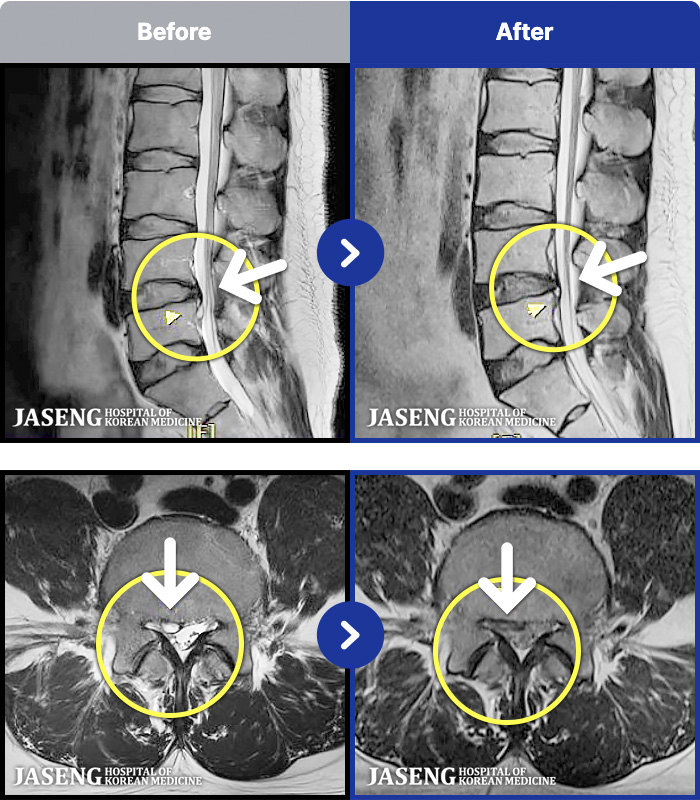

[] 23.11.11~25.06.04